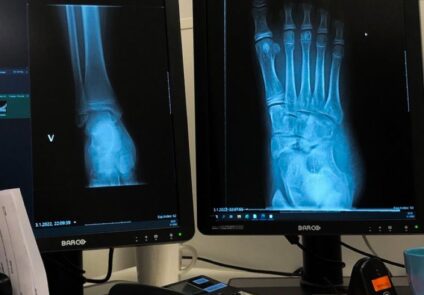

Explore in-depth patient journeys from The Ortho Clinic, highlighting expert diagnosis, personalized orthopedic care, and life-changing recovery outcomes.